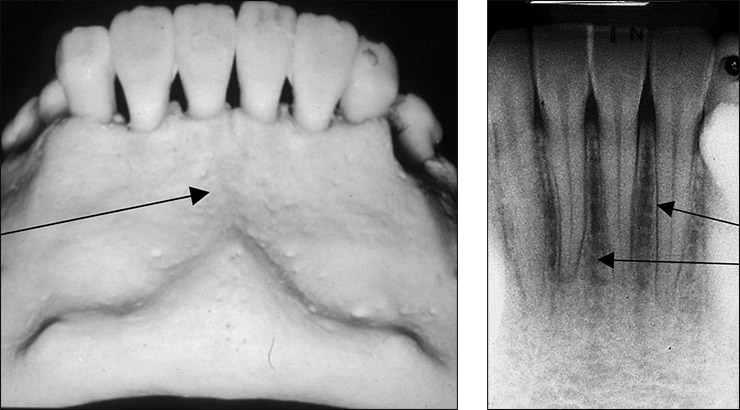

what is this, its description and its appearance on images

incisive canal

passageway thru bone that extends from superior foramina from incisive canal to foramen

tubelike radiolucent area with radiopaque borders, can be seen intraoral img

incisive foramen

hole in bone located at midline of anterior hard palate directly posterior to maxillary central incisors

round radiolucency located btween roots of maxillary central incisors, can be seen intraoral img